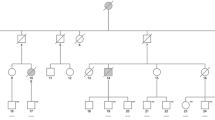

The variants were annotated using wANNOVAR (wannovar.wglab.org) [28] and analyzed using multiple computational software programs to predict the effect of these variants (Functional Analysis Through Hidden Markov Models (FATHMM) [29], MutationTaster [30], Sorting Intolerant from Tolerant (SIFT) [31], Polymorphism Phenotyping v2, Human Variants Database (Polyphen2 HVAR) [32], Likelihood Ratio Test (LRT), Combined Annotation Dependent Depletion (CADD) [33], Mendelian Clinically Applicable Pathogenicity (M-CAP) [34]). Identified variants were classified following the recommendations of the American College of Medical Genetics and Genomics (ACMG) [35]. The current literature (up to June 2024) was searched using the NCBI National Library of Medicine (PubMed) to determine that the variants were not reported previously. Genetic data are summarized in Fig. 1 and Table 2.

Genomic organization and protein domain structure of CSF1R with characteristics of novel CSF1R variants. The CSF1R gene spans more than 60 kbp and contains 21 exons (transcript ID: ENST00000675795.1). It encodes a protein of 972 amino acids (protein ID: ENSP00000501699.1), containing five extracellular immunoglobulin domains, a transmembrane domain as well as an intracellular tyrosine kinase domain. The six novel variants are all located in the tyrosine kinase domain. Their respective amino acids are evolutionarily conserved, as confirmed through alignment with several species. The schematic displays the names and RefSeq IDs of the species used for the alignment with the human reference sequence of the CSF1R protein

Protein alignment

To determine the evolutionary conservation of the CSF1R protein, the amino acid sequence was compared among different species (human, RefSeq NP_001275634.1; chimpanzee, RefSeq XP_016809515.1; rhesus macaque, RefSeq XP_001107711.4; cattle, RefSeq NP_001068871.2; dog, RefSeq XP_546306.2; cat, NP_001009231.1; sheep, RefSeq XP_027826197.2; rat, RefSeq NP_001025072.1; mouse, RefSeq NP_001032948.2; chicken, RefSeq NP_001308446.2; frog, RefSeq NP_001008181.1) using Jalview (jalview.org) [36] (Fig. 1).